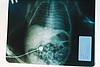

В середине ноября в Кировскую областную детскую клиническую больницу поступил новорожденный ребенок с редкой патологией развития – диафрагмальной грыжей. Как рассказала мама малыша, на 34 неделе беременности наступили роды, на свет появились два мальчика, у одного из которых врачи заподозрили достаточно редко встречающееся заболевание. Маленькому пациенту была проведена рентгенография в стенах Перинатального центра, после чего он был направлен в Детскую областную больницу для проведения операции.

– Диафрагмальная грыжа встречается достаточно редко, в нашей практике на 10 тысяч новорожденных приходится лишь один случай. Эта патология опасна тем, что выживаемость маленьких пациентов составляет всего 50% из-за того, что органы из брюшной полости через отверстие в диафрагме перемещаются в грудную полость и не дают легкому полностью раскрыться, – рассказал заведующий хирургическим отделением Кировской областной детской клинической больницы Виталий Лапшин. – Таким пациентам мы проводим малоинвазивные операции. Через небольшие проколы с помощью инструментов, самый маленький из которых толщиной всего 2 миллиметра, мы перемещаем необходимые органы на место в брюшную клетку и зашиваем диафрагму.

– Малыш поступил к нам с весом чуть более 2,5 килограмм, у него было отверстие в диафрагме размером почти три сантиметра. Представьте, как непросто врачам проводить операции таким маленьким пациентам. Это требует особого мастерства, собранности и внимательности. Благодаря имеющейся в нашей больнице современной видеоэндоскопической стойке специалисты проводят сложнейшие, а иногда и уникальные операции, спасая даже самых маленьких пациентов. Здесь важна командная работа, активное взаимодействие врачей-хирургов, реаниматологов, неонатологов и педиатров позволяет сохранить жизни детей, помочь им восстановить здоровье, – сообщила главный врач Кировской областной детской клинической больницы Наталья Муратова.